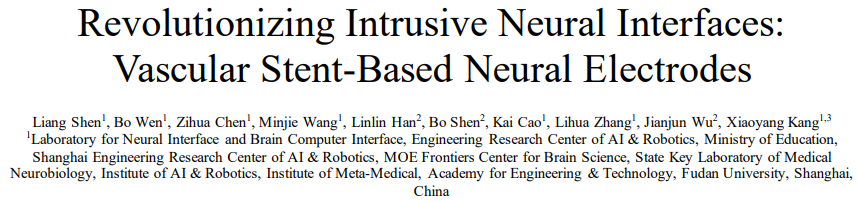

支架电极已成为脑电极领域的一种很有前途的选择。支架的直径极小,可以进入血管而不影响血液循环。通过固定支架结构上的电极点,可以收集信号或在大脑深处进行电刺激。这提供了一种相对非侵入性的方法来获取和操作神经活动。图1显示了x射线下支架电极的形态和体内状态。

图 1 支架在绵羊上矢状窦(SSS)中的部署的x线图像